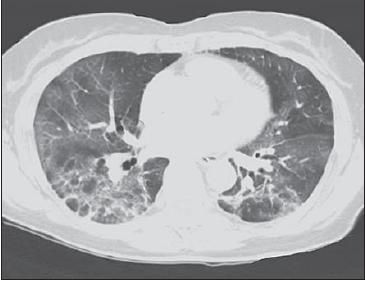

A chest radiograph obtained 2 weeks before presentation showed mild increased interstitial markings and hyperinflation (Figure 1A). A chest radiograph obtained on presentation showed new bilateral pulmonary infiltrates (Figure 1B). A CT scan of the chest showed diffuse bilateral ground-glass infiltrates (Figure 2).

Figure 2 – CT scan of the chest revealed diffuse bilateral ground-glass infiltrates.